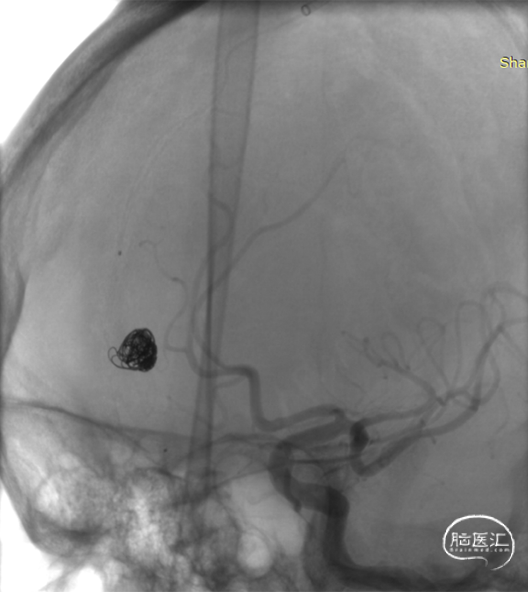

近端静脉球弹簧圈致密栓塞后,经马拉松微导管注入Onyx18。

顺利“安全”地注入Onyx18,瘘口完全栓塞,造影提示一期治愈,正常皮层引流静脉得以保留。

术后即刻造影见DAVF完全栓塞。